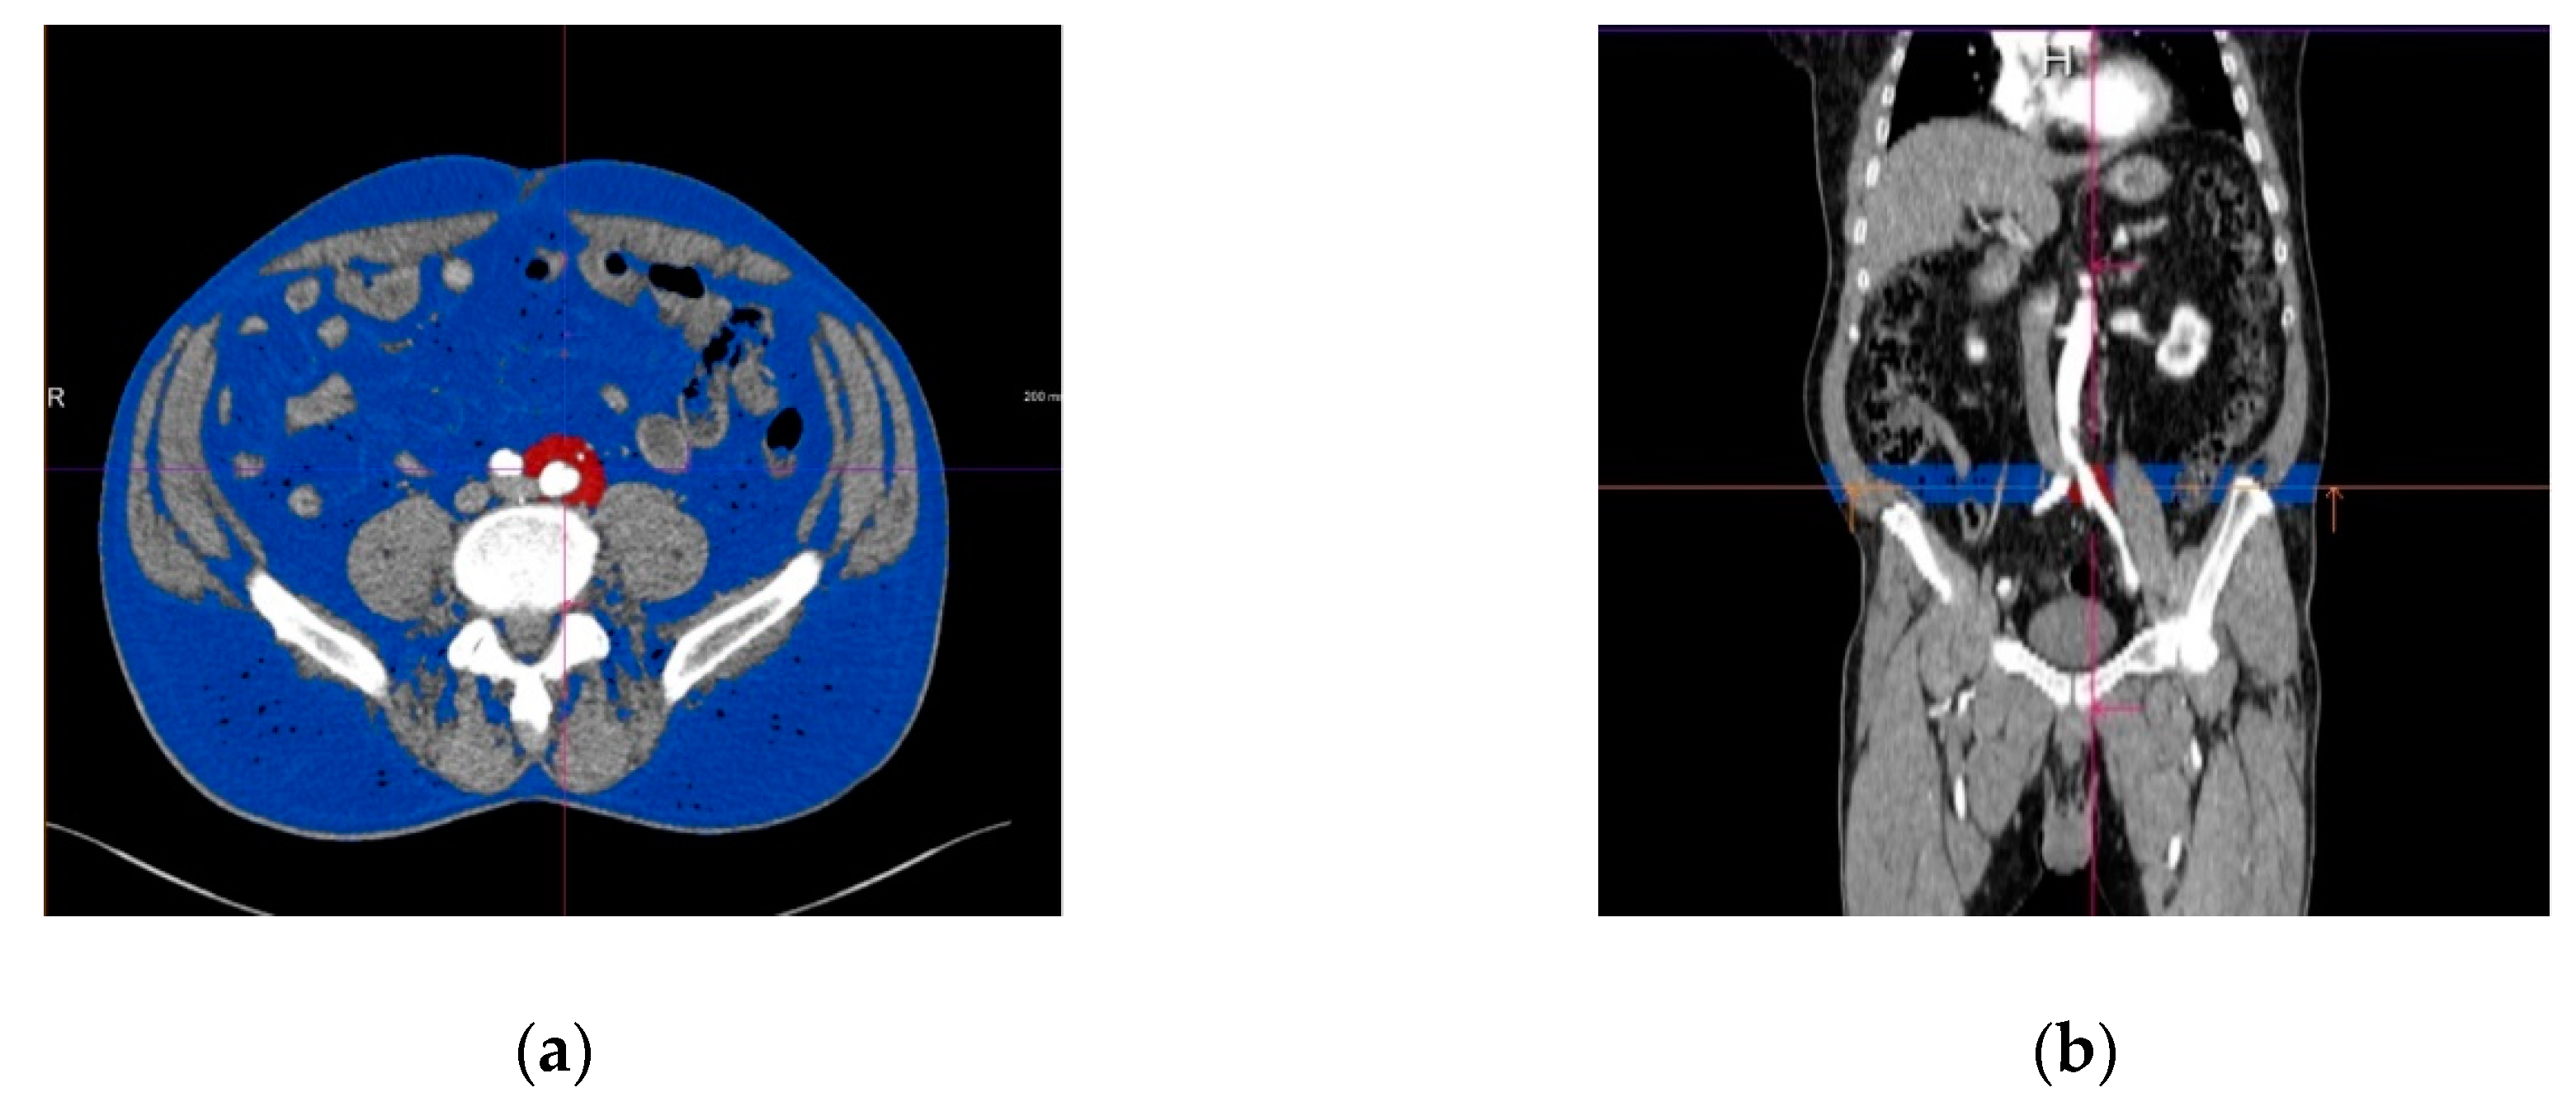

2.3. Assessment of the Periiliac Adipose Tissue